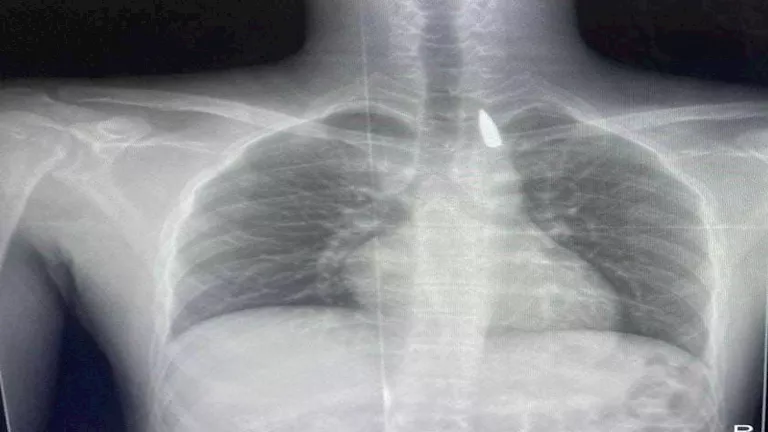

كان المريض الفلسطيني، تعرض لإصابة بطلق ناري في الرأس منذ فترة، استقر المقذوف على إثرها داخل تجويف القفص الصدري قرب الشريان الأورطي، وهو أكبر وأهم شرايين الجسم والمسؤول عن تغذية جميع الأعضاء الحيوية.

وأوضح الدكتور تامر عبد الله، عميد كلية الطب جامعة الإسكندرية، ورئيس مجلس إدارة المستشفيات الجامعية، أنه رغم دقة الحالة وتعقيدها إلا أن الفريق الطبي نجح في استخراج المقذوف بأمان بعد عملية جراحية نادرة.